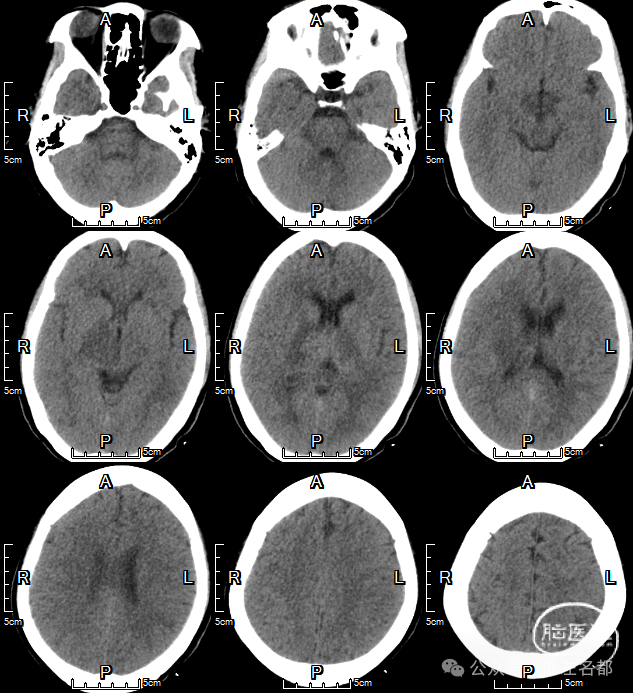

急诊多模式CT

2024-9-23 07:50

CT平扫:双侧丘脑低密度肿胀,直窦-大脑大静脉血栓高密度。

2024-1-26 术后即刻

CT平扫:双侧丘脑静脉梗死区域造影剂染色。

2024-1-27 术后第2日

CT平扫:右侧丘脑静脉梗死区稍高密度。

2024-10-2 术后第7天

CT平扫:双侧丘脑病变范围明显改善。

2024-10-14 术后第19天

CT平扫:仅见右侧丘脑和内囊少许低密度影。